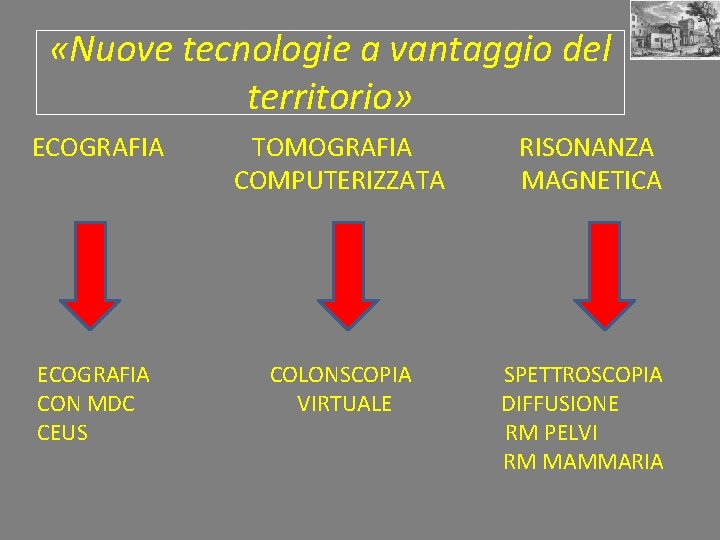

«Nuove tecnologie a vantaggio del territorio» ECOGRAFIA TOMOGRAFIA COMPUTERIZZATA ECOGRAFIA CON MDC CEUS COLONSCOPIA VIRTUALE RISONANZA MAGNETICA SPETTROSCOPIA DIFFUSIONE RM PELVI RM MAMMARIA